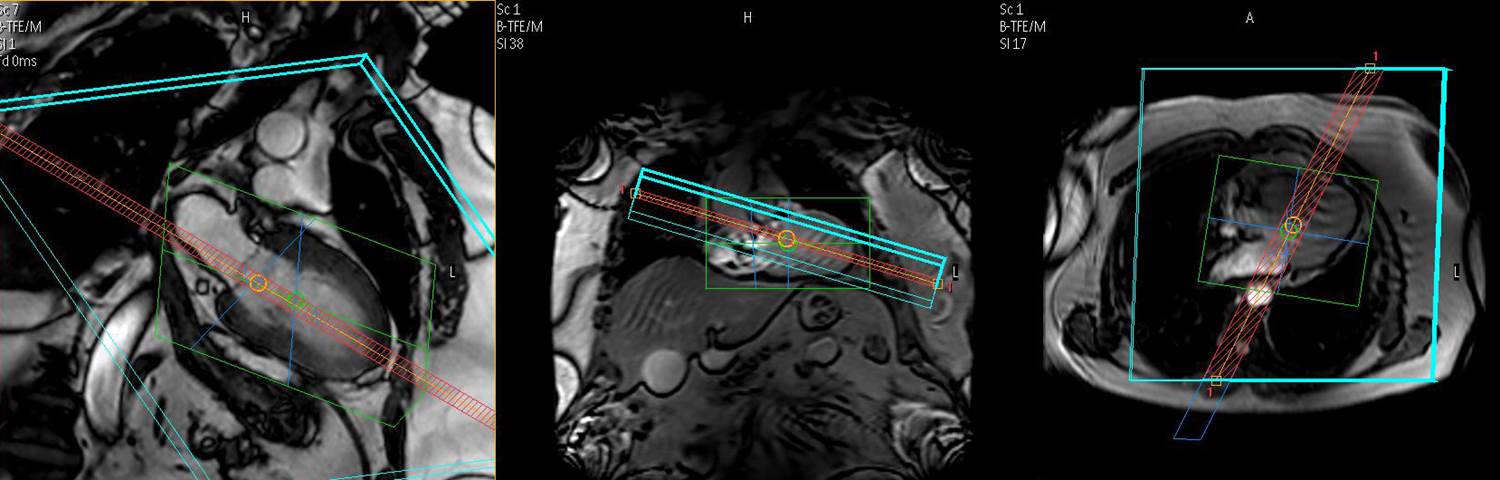

This level 2 fellowships covers the basics of CMR along with advanced education required to enable attendees to independently conduct standardized CMR examinations. It provides the preparation for routine clinical use of CMR with all necessary theoretical and practical background including workflow aspects. Courses are structured according to the “Level 2” - credentialling criteria.

- CMR indications and methods of interpretation

Supervised interpretation of more than 250 CMR studies representing the range of abnormalities observed in practice including both cardiac and vascular studies.

- Imaging of the coronary arteries